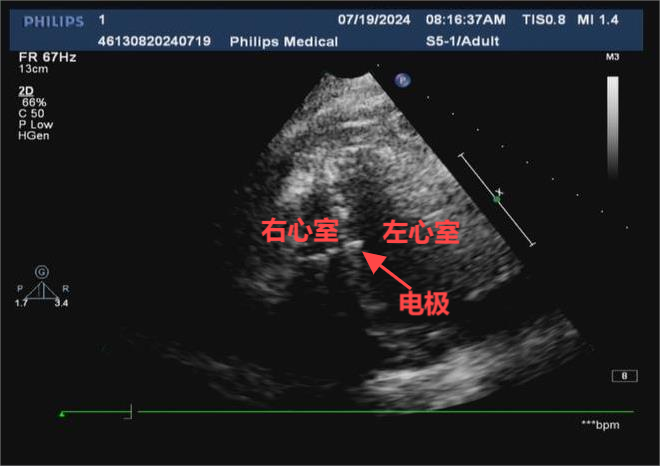

心血管内二科周玉庆副主任医师、李华锋主治医生为老人顺利完成该项手术后,患者术后起搏心电图呈窄QRS波,双极起搏模式甚至纠正了肖老右束支传导阻滞,超声影像也证实电极已送至左室间隔内膜下。肖老心功能明显改善,术后恢复顺利,目前已康复出院。